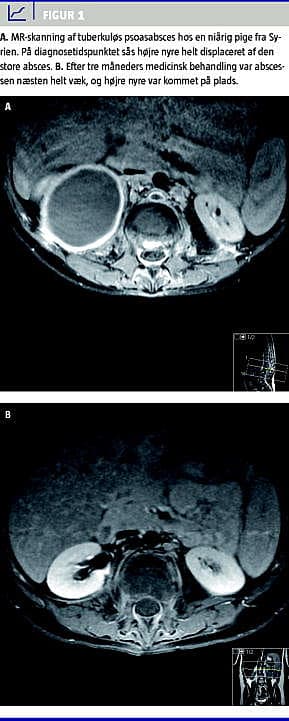

Den hyppigste form for tb i knogler og led er spondylitis tuberculosa (Potts sygdom) efterfulgt af artritis i de vægtbærende led og osteomyelitis uden for columna. Spondylitis tuberculosa sidder oftest i torakalcolumna. Infektionen begynder i den forreste del af corpus vertebra, hvorefter den breder sig til en discus intervertebralis og næste vertebra. Der kan udvikles abscesser paraspinalt eller som psoasabsces (Figur 1 ). Symptomerne begynder med lokaliserede smerter og almene symptomer, men der kan senere komme rodpåvirkning med lammelser til følge. Diagnosen stilles ofte på den kliniske mistanke kombineret med typiske forandringer, der kan ses på en magnetisk resonans (MR)-skanning, da det kan være vanskeligt at få materiale til mikroskopi og dyrkning [12].